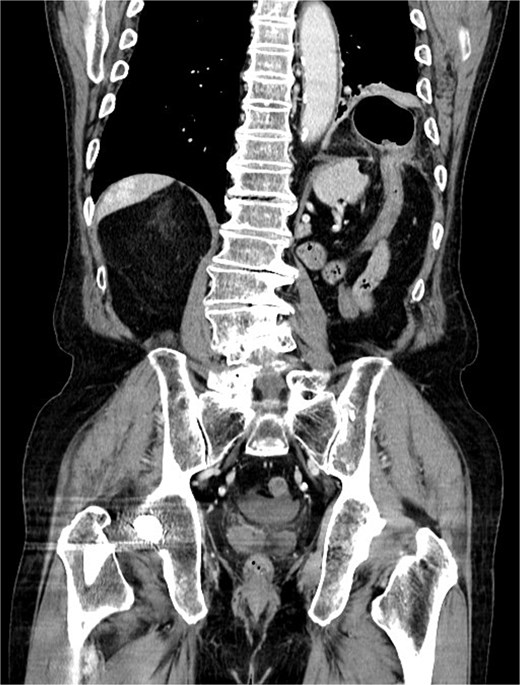

An 81-year-old man presented to our clinic with epigastric pain and nausea lasting 2 days. His medical history was significant for bladder stone surgery, left inguinal hernia repair, right hip surgery, prostate cancer, ascending colon cancer, chronic kidney disease, hypertension, and a laparoscopic left nephrectomy for upper tract urothelial carcinoma performed 5 years prior to the current presentation. Initial abdominal computed tomography (CT) showed no evidence of bowel obstruction, and the patient was discharged home. However, the following morning, he developed worsening nausea and vomiting and revisited our clinic. Abdominal radiography revealed air–fluid levels in the small intestine and intrathoracic bowel gas in the left lower lung field. Repeat abdominal CT demonstrated herniation of the transverse colon into the left thoracic cavity (Fig. 1). He was urgently referred to a critical care medical center with suspected obstructive ileus.

Coronal contrast-enhanced computed tomography image demonstrating a left-sided diaphragmatic defect with herniation of the transverse colon into the left thoracic cavity. No radiological signs of bowel strangulation were observed.

Contrast-enhanced CT revealed herniation of the transverse colon through a left posterolateral diaphragmatic defect, consistent with an incarcerated BH. Emergency laparotomy was performed via a transabdominal approach. Intraoperatively, a left-sided diaphragmatic defect was identified on the anterior surface of the spleen, through which the transverse colon at the splenic flexure and the greater omentum were herniated and incarcerated. The initial defect measured approximately 25 × 25 mm. However, to allow safe reduction and adequate assessment of the incarcerated contents, the defect was intentionally enlarged to approximately 70 × 60 mm. Partial discoloration of the herniated omentum was observed, and the affected portion was resected. The transverse colon was adherent but showed no evidence of perforation. Although a small amount of ascites was present, there were no signs of intra-abdominal contamination. The diaphragmatic tissue surrounding the defect appeared healthy and without fragility, therefore, primary closure was achieved using interrupted sutures. Mesh reinforcement was not applied, as tension-free closure was possible and no tissue weakness was observed. The postoperative course was uneventful, and the patient was discharged on postoperative day 9.